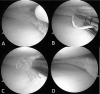

Interventions: The method uses Fast-Fix, whereby a first anchor is inserted from the tibial surface of the tear's superior leaflet and a second anchor is inserted from the femoral surface of the tear's inferior leaflet, and the 2 leaflets are closed using vertical suture. In all cases, the suture knots were embedded between the superior leaflet and inferior leaflet, avoiding contact with the articular cartilage, and superior leaflet and inferior leaflet crimping was good.

Lessons: The all-inside interleaf vertical suture procedure is a new surgical technique that can repair posteromedial horizontal meniscal tears of the knee of young people by easy crimping of the superior and inferior leaflets without the suture knots causing complications.